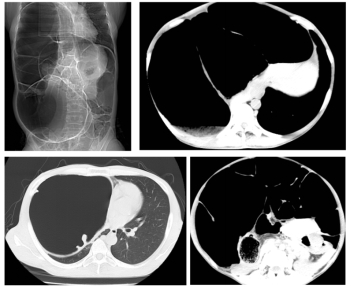

家住佳木斯40岁的陈女士,被便秘困扰20余年,长期遭受便秘的折磨,近年间症状持续加重,排便周期长达7日并伴随剧烈腹胀。陈女士在beat365在线唯一官网附属第一医院群力院区行CT检查,腹腔内盲肠、升结肠、横结肠、降结肠及部分乙状结肠严重扩张积气,移行段位于乙状结肠,以造成右侧膈肌上移压迫右肺。群力院区普外科一病房(结直肠外科)朱跃坤教授诊断为特发性巨结肠。